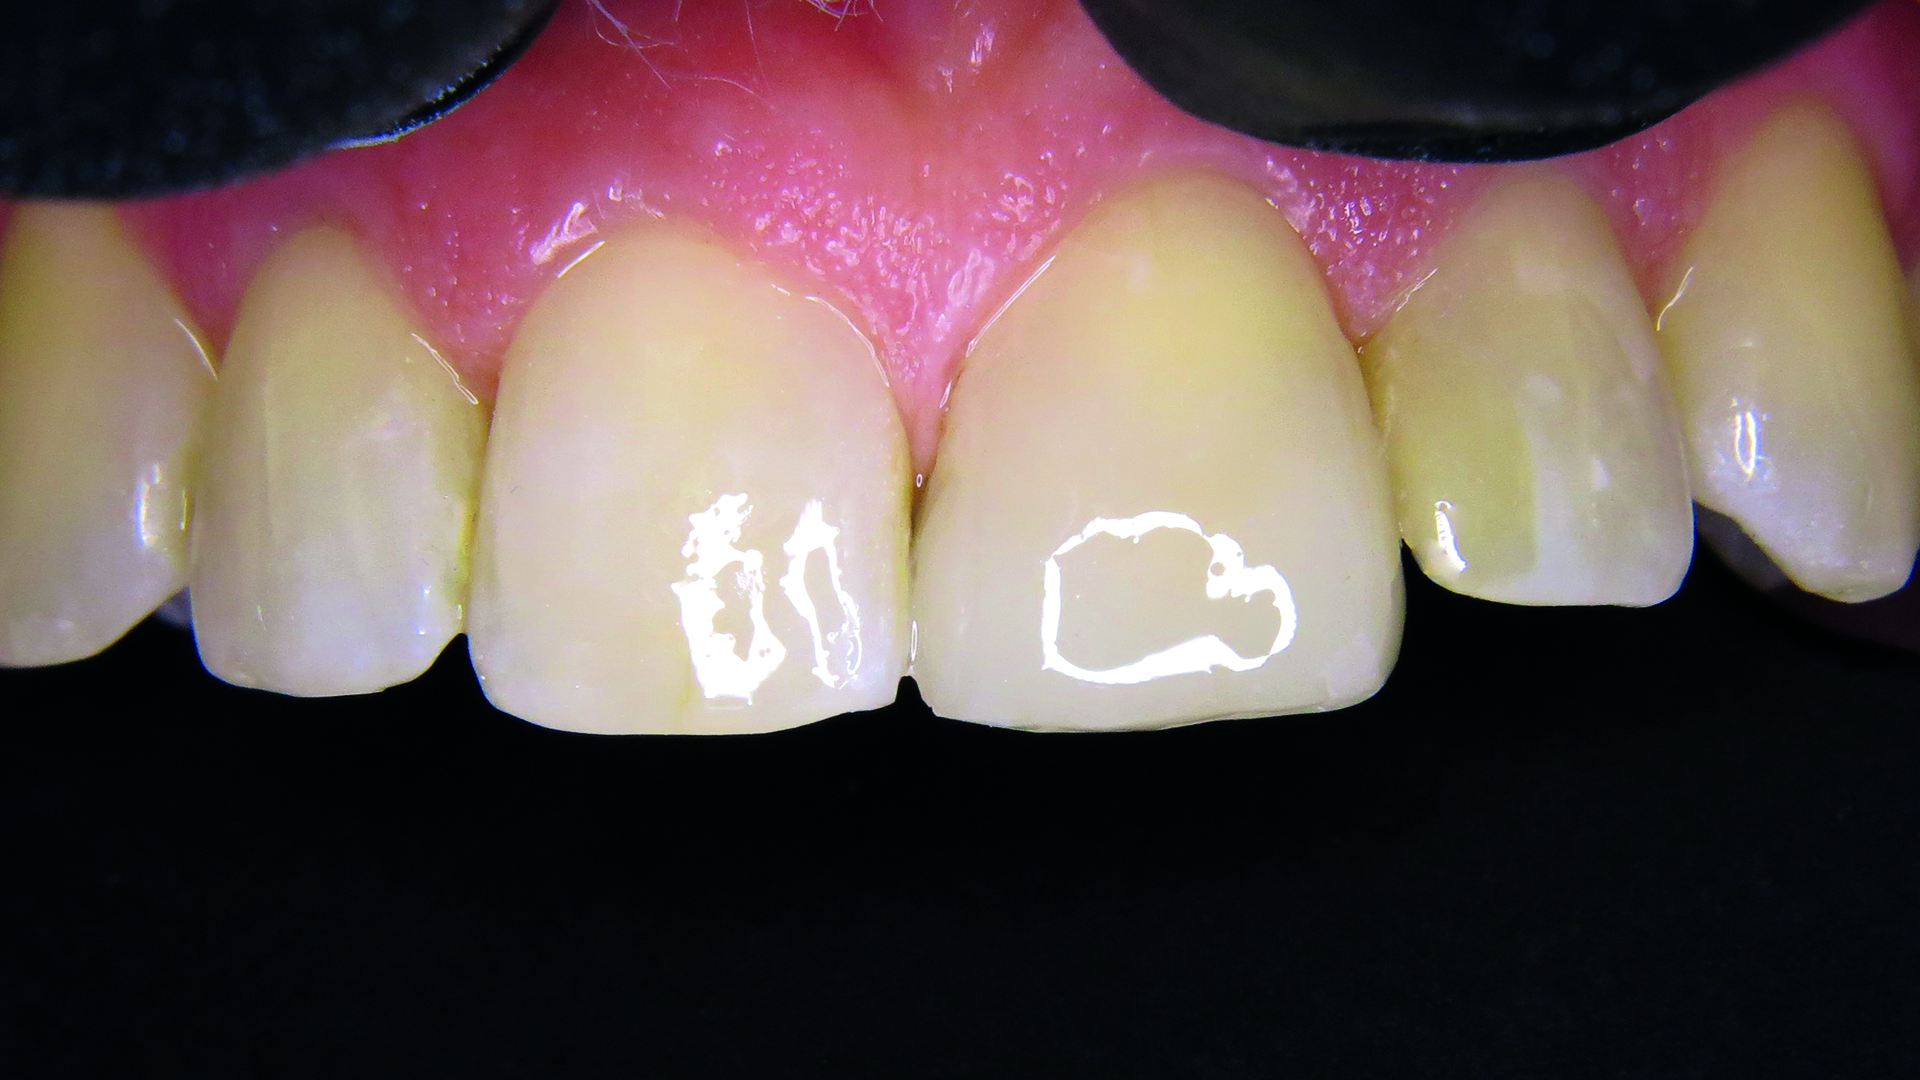

Z gamy odcieni klastrowych wybrano odcień A2 (ryc. 2). Następnie pobrano wycisk masą V-Posil Putty Fast (VOCO GmbH, Niemcy) w celu stworzenia modelu gipsowego. Z materiału Registrado Clear (VOCO GmbH, Niemcy) wykonano indywidualny klucz silikonowy do nadbudowy powierzchni podniebiennej (ryc. 3).

Ryc. 2. Łatwy dobór odcienia.